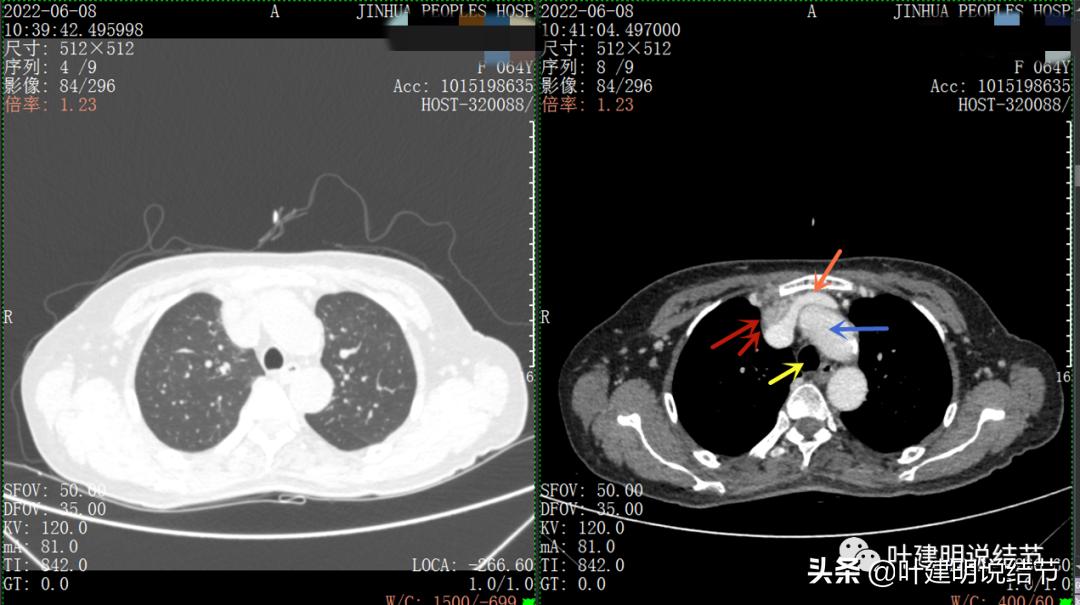

以下图片左侧是肺窗,右侧是纵隔窗。红色箭头示病灶,桔色箭头示无名静脉,黄色箭头示支气管,砖色箭头示上腔静脉,蓝色箭头示主动脉,紫色箭头示肺动脉。

绿色箭头示近膈面处,心脏边病灶

此灶与主病灶不是完全相连的

特别显示与无名静脉的关系